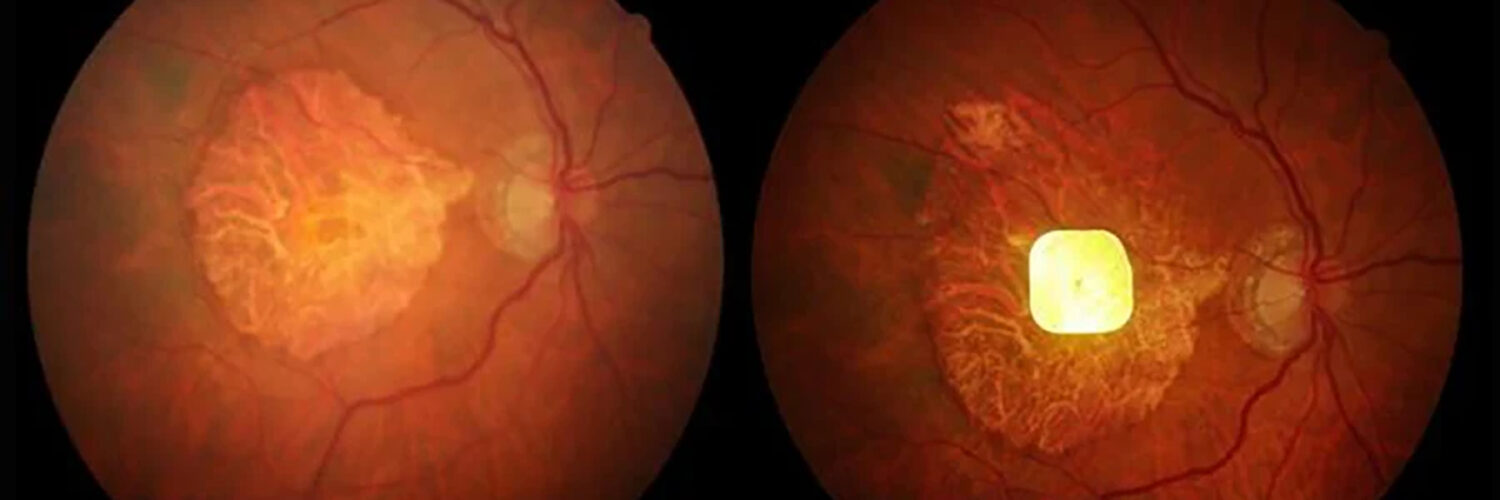

Pocas condiciones suponen un reto tan complejo como la Degeneración Macular Asociada a la Edad. El Sistema de Visión Biónica PRIMA se presenta como el primer salto cuantitativo probado hasta la restauración de parte de la visión funcional.

El paciente con DMAE que llega a una consulta de baja visión no es un paciente ciego: es un paciente con pérdida central bilateral y visión periférica funcionalmente preservada. Comprender este perfil antes de abrir la historia clínica condiciona toda la estrategia rehabilitadora. Esta miniguía abarca desde la evaluación funcional hasta la rehabilitación y coordinación multidisciplinar.